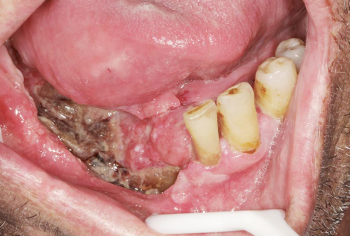

Les cancers de la cavité buccale, dont le taux de survie à cinq ans n’a pas évolué au cours des trente dernières années, sont un véritable problème de santé public, de par leur incidence, la morbidité et la mortalité qui en découlent. La majorité de ces cancers sont, malheureusement, encore de nos jours diagnostiqués à un stade tardif ce qui diminue fortement la chance de survie du patient, entraîne une chirurgie mutilante et une qualité de vie moindre. Le chirurgien-dentiste est un des acteurs qui peut remédier à cette fatalité en réalisant un examen clinique systématique de la cavité buccale quand un patient se présente à son cabinet. Examen rapide, facile à réaliser, indolore, nécessitant peu d’instruments, il est efficace pour détecter la moindre lésion buccale, et permet un diagnostic précoce de cancer. Seule la biopsie peut confirmer la nature maligne de la lésion et aucune autre technique ne peut se substituer à celle-ci. Il n’est plus acceptable de détecter un cancer de la bouche à un stade avancé. Les chirurgiens-dentistes doivent absolument s’impliquer dans l’examen systématique de la cavité buccale et le diagnostic précoce des lésions suspectes.

Le pronostic de ces cancers reste très péjoratif, le taux de survie à 5 ans est de 35 % tous stades confondus, il ne s’est guère amélioré au cours de ces dernières décennies [4, 5]. Les cancers de la LBP sont à plus de 90 % des carcinomes épidermoïdes, c’est-à-dire qu’ils se développent à partir de l’épithélium buccal [2]. Ainsi, toute altération, même minime, de la muqueuse…